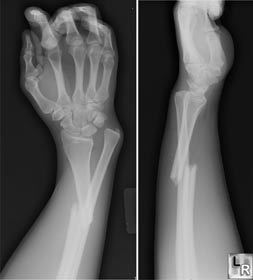

有一个小孩,她非常的不幸,有一次她放学,在人行道上时,突然,人群大乱,从那边冲来了一个刹车失灵繁荣一辆奔驰汽车,一连撞到了4名学生,其中就包括这个不幸的孩子----谢晓荣,她被撞的满脸是血,经过检查,她全身7处骨折,其中包括3处粉碎性骨折,医院决定为她输血,经过验血,谢晓荣是AB型血,第二天早上,医院为她输了800毫升的AB型血,还好没有伤到利害部分,我真是为了她松了一口气,5天之后,医院为她做了骨折复位手术,用一个特制钢板固定住了多处断裂的地方,医院又为她输了2000毫升的血,突然,紧急状况发生了,她浑身直哆嗦,但是一会儿有好了,第8天后,她的身体又可以进行第2次手术了,这次是取下身体里的东西,把2块钢板和16颗钢钉取下来,医生对她的母亲说为她手术准备的800毫升的血不能用了,妈妈说:“没关系,把我的血献给她。”医生说:“不行。”因为妈妈是AB型阳性血,这种阴性血极少,可以说是少中之少个汉族人只有两个人是RH阴性血。母亲疑惑了,决心查清此事,原来是医院输错了血,灾难又一次降临到她不幸的女儿身上。妈妈经过不懈的努力,为女儿讨回说法。